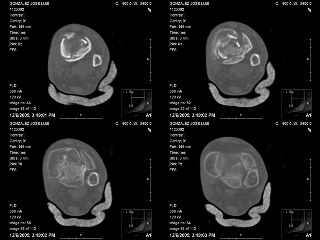

A 56 year old laborer fell off a wall approximately 5 months ago. He sustained an open pilon fracture. He was treated with debridement and external fixation. After he was treated for 4 months, the external fixator was removed.

The patient had no medical insurance and was therefore transferred to my care by his treating surgeon. He has remained NWB. He denies pain in his ankle. He has painless dorsiflexion and plantarflexion of his ankle joint.

I have attached his x-rays. I have also attached an WMV movie file of his axial CT (if you are unable to view this, I can post an MPEG file).

Suggestions for treatment?